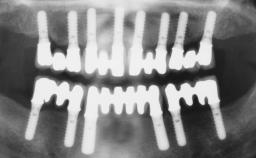

A fully edentulous 65-year-old woman was referred to our clinic for esthetic and functional dental rehabilitation. The patient presented with inadequate complete maxillary and mandibular prostheses, insufficient vertical dimension, and extensive tooth wear. The clinical examination and anamnesis showed no local or systemic contraindications, no signs or symptoms of bruxism, and an absence of smoking habits. The treatment proposed was implant placement in the mandibular interforaminal area and immediate loading with a fixed definitive prosthesis. A removable mucosa-supported complete prosthesis was indicated for the upper jaw, since its bone structure offered satisfactory retention and the financial condition of the patient disfavored a full-mouth implant-supported rehabilitation.

# of Implants 4

Type of Implants One-Piece

Attachment One-Piece

Prosthesis Type FDP

Loading Protocol Immediate

Retention Screw-retained, with 4 or more splinted implants Screw-retained, with 4 or more splinted implants